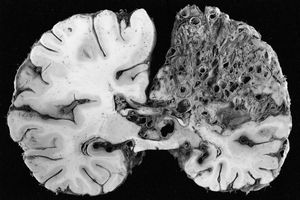

신경병리학은 신경계 조직의 질병에 대한 연구이며, 일반적으로 수술 생검이나 부검의 경우 전체 뇌의 형태로 이루어진다. 신경병리학은 해부 병리학, 신경학, 그리고 신경외과의 하위 전문 분야이다.

일상적인 임상 실무에서 신경병리학자는 환자를 위한 진단을 내린다. 신경계 질환이 의심되고 덜 침습적인 방법으로 진단을 내릴 수 없는 경우, 진단을 돕기 위해 뇌나 척수에서 신경 조직 생검을 시행한다. 생검은 일반적으로 의료 영상으로 종괴가 감지된 후에 요청된다. 부검 시, 신경병리학자의 주요 업무는 중추 신경계에 영향을 미치는 다양한 상태의 사후 진단을 돕는 것이다.